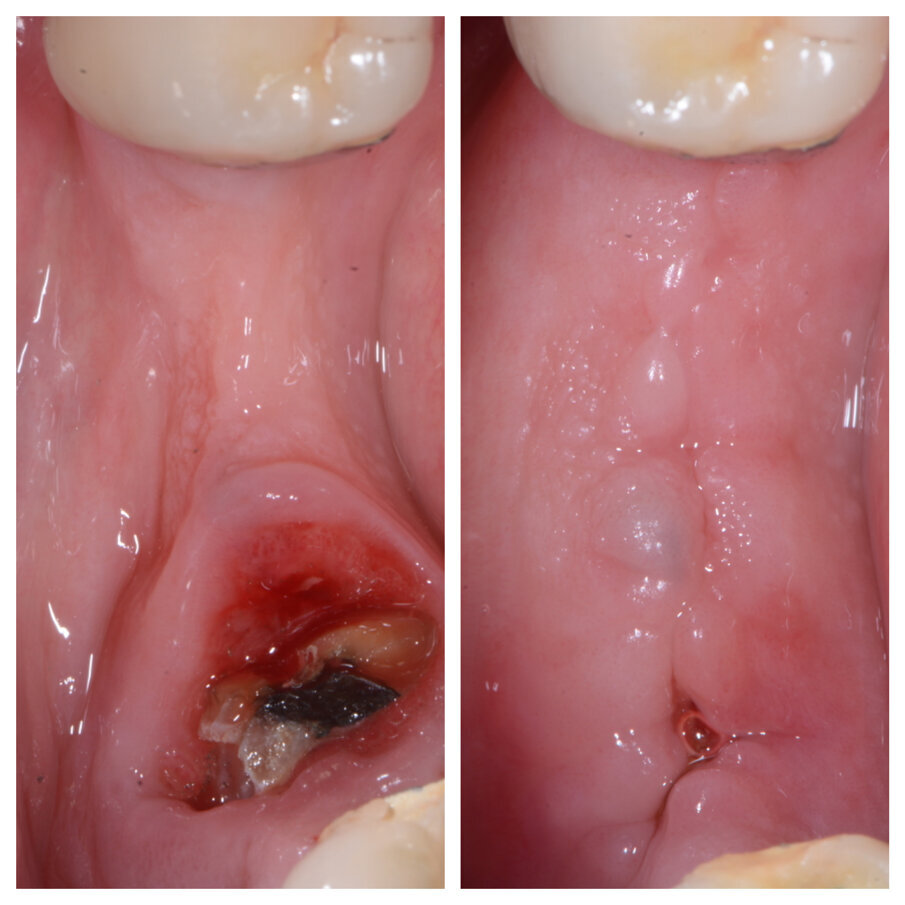

Fig. 1b_Cambiamento dei tessuti a 22 giorni.

Fig. 3a_Tecnica S.A.T. applicata in zona 44-45-46.

Fig. 3b_Cambiamento dei tessuti a 27 giorni.